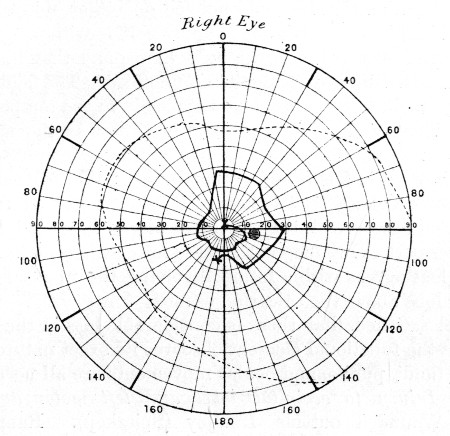

75. " " " 281

76. " " " 281